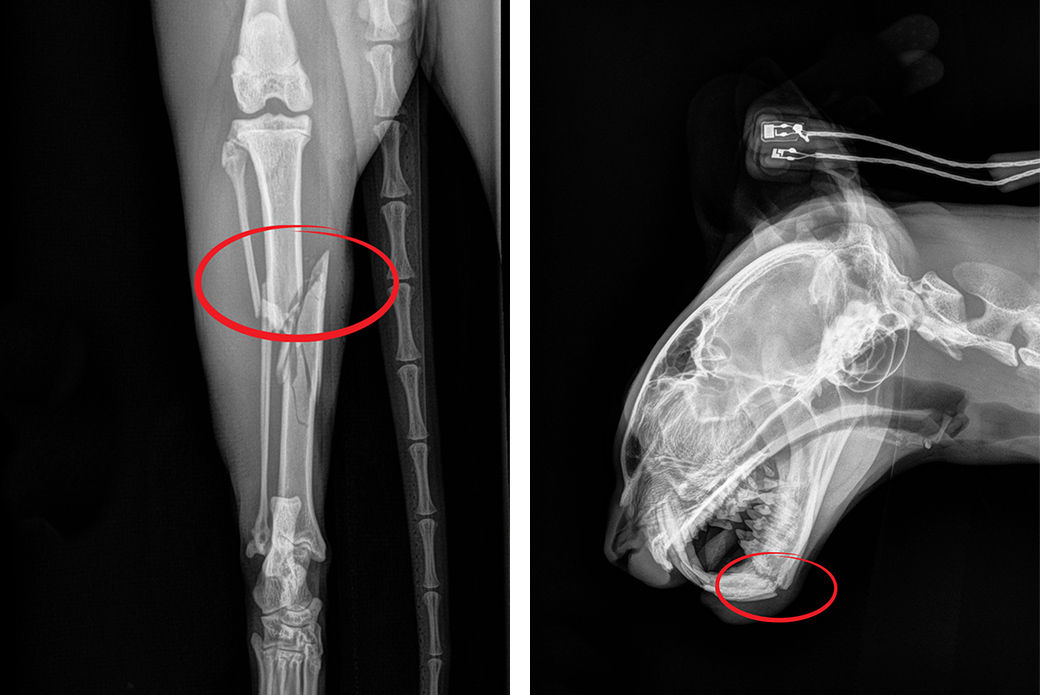

“He had a right hind leg fracture—both tibia and fibula—and a broken jaw and broken teeth, likely due to falling from a high-rise building,” says Dr. Bliss. “He was in so much pain and distress and he was so fearful—hissing, growling and lunging. But I thought, ‘If this were my cat, and he had this horrible accident, I would want him back.’ He was in so much pain we could hardly handle him.”

Pain from his jaw fracture made it difficult for Oslo to eat, so an esophageal feeding tube was placed on the side of his neck. On December 30, Dr. Anna Whitehead amputated his leg. Oslo was also treated for an upper respiratory infection and given gabapentin, a typical behavior medication that also works as an effective analgesic.

High-rise syndrome is unfortunately seen far too frequently and is preventable with proper safety measures. As of May 31, 2023, veterinarians at the ASPCA Animal Hospital have treated 21 cases of high-rise syndrome. In 2022, 45 cases. The most common injuries associated with these incidents are shattered jaws, bruised or punctured lungs, and broken limbs and pelvises.